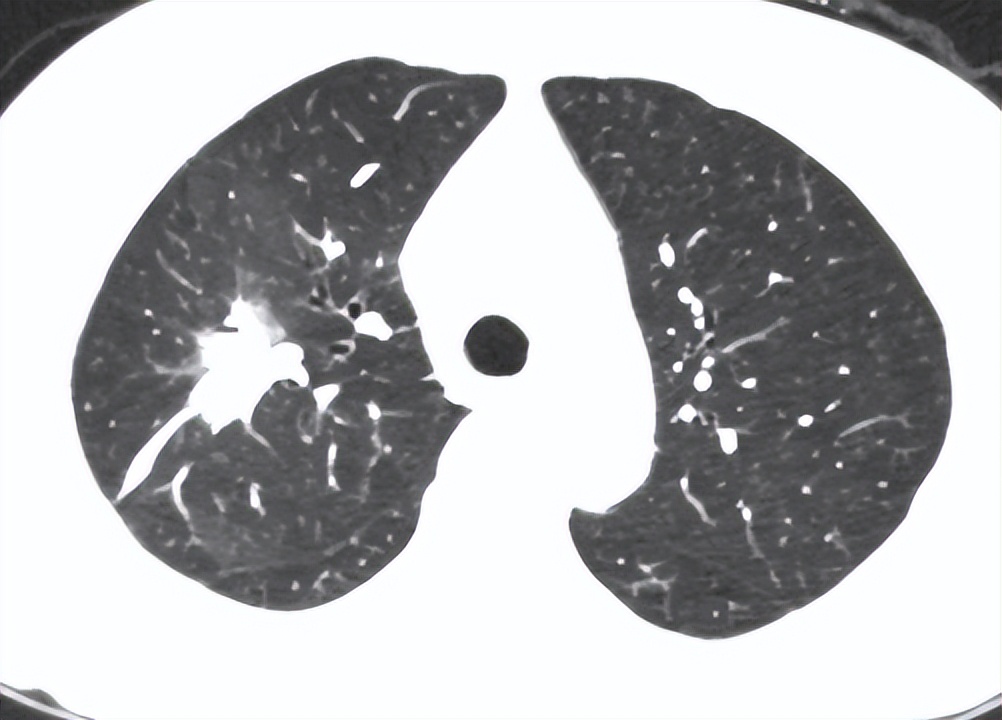

患者院外的CT提示:右肺上叶占位2.4*3.2cm。为了进一步明确患者肺部病变的性质,患者入院后我们立即完善了肺部增强CT: 右肺上叶肿块影,大小约31*25mm,增强可见轻度强化,其内支气管部分截断,周边可见毛刺,邻近胸膜牵拉,考虑肿瘤性病变 。

邀请放射科医生和肿瘤科医师仔细阅读后,该病变的位置可以通过经皮肺穿刺获取明确的诊断。在征得了患者家属同意后,我们给患者安排了肺穿刺检查,检查结果提示: 肺腺癌 。

患者右上肺病变 图片来源 :讲述者提供